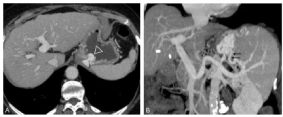

Les voies de dérivation veineuses (ou shunts) portosystémiques se développent avec en particulier des varices œsophagiennes (figure 5.4).

Retenons qu’il existe cinq grands groupes de varices : œsophagiennes et gastriques, splénorénales, pariétales et para-ombilicales, mésentériques et périrectales, et enfin rétropéritonéales. Une ascite apparaît.

Fig. 5.4 Varices gastriques. Scanner.

Coupes axiales (A) et coronales obliques (B) de scanner acquises au temps portal après injection IV de produit de contraste iodé. Au sein de l’estomac fait saillie une volumineuse varice gastrique (tête de flèche). Celle-ci est à risque très élevé de rupture et donc d’hématémèse. La visualisation coronale oblique permet d’identifier l’origine du paquet variqueux : une veine gastrique postérieure naissant de la veine splénique (flèches fines).

Source : CERF, CNEBMN, 2022.